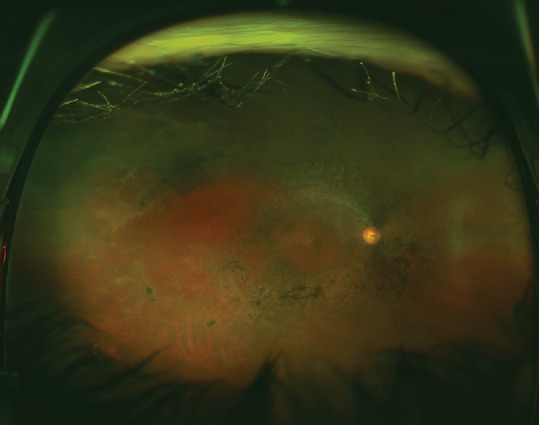

Multimodal imaging and genetic testing allow sophisticated assessment of suspected inherited retinal disease. Given the availability of such technology, some question whether the full-field electrogram (ffERG) is needed anymore. In fact, a ffERG remains essential for certain clinical scenarios. The goal of this case-based review is to provide a clear understanding of what clinical situations warrant a ffERG. All practicing ophthalmologists should be familiar with this information.